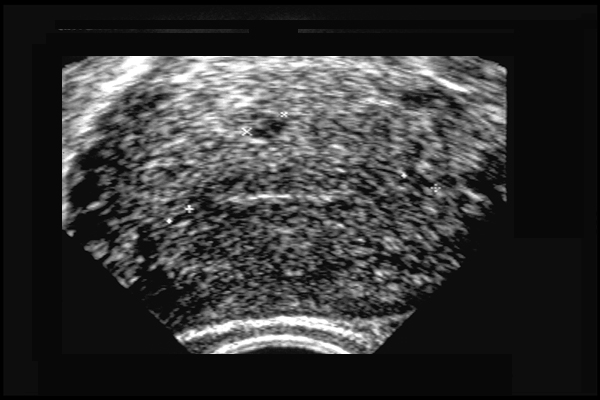

Adénomyose utérine. Coupe transversale - myomètre hyperéchogène hétérogène avec cavités de petite taille (+) - gros utérus.